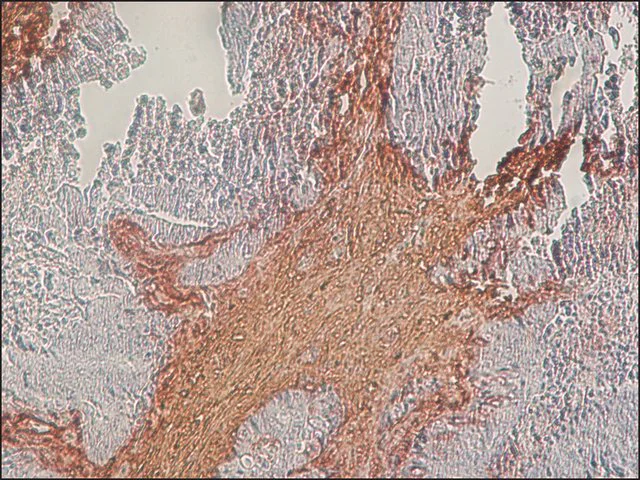

Immunohistochemistry (Formalin/PFA-fixed paraffin-embedded sections) - Anti-Chondroitin Sulfate antibody [CS-56] (AB11570)

Immunohistochemical analysis of formalin-fixed, paraffin-embedded human colon cancer sections labelling chondroitin sulfate with ab11570 at 1/2500 dilution.